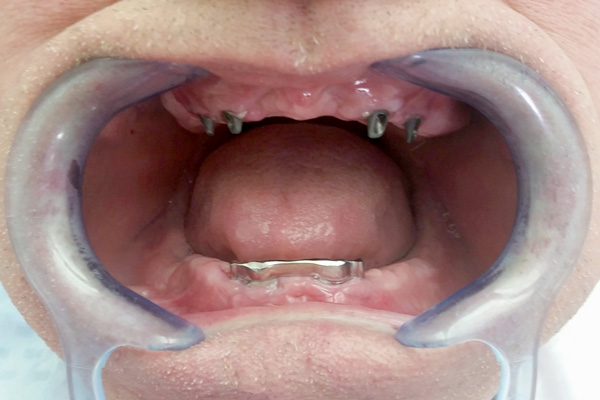

Overdenture

Overdentures are semi-fixed dentures are placed on dental implants. They are held in places in the jaw with precision attachments: either a sphere or a bar. Overdentures are can easily be removed for cleaning and they are held firmly in place while eating or speaking.